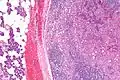

| Micrograph of an acinic cell carcinoma (right of image) and acinar glands (parotid gland - left of image). H&E stain. | |

Basophilic, bland cells similar to acinar cells. Growth pattern: solid - acinar cells, microcytic - small cystic spaces mucinous or eosinophilic, papillary-cystic - large cystic lined by epithelium, follicular - similar to thyroid tissue.

These tumors, which resemble serous acinar cells, vary in their behavior from locally aggressive to blatantly malignant.

Intermed. mag.

Very high mag.